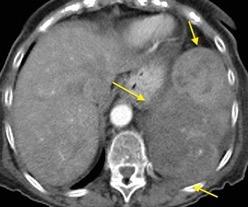

Nefrectomia derecha en 1996 por adenocarcinoma renal. Reseccion de metastasis pulmonar en LSI de carcinoma renal. Sospecha de nueva metástasis.

Granuloma de cuerpo extrano por hilo de sutura en situación cisural

Madan Ret al. Intrathoracic gossypiboma. AJR 2007/Anderson JM et al. FOREIGN BODY REACTION TO BIOMATERIALS. Semin Inmunol 2008/Okazaki M et al. Two cases of granuloma mimicking local recurrence after pulmonary segmentectomy. Journal of Cardiothoracic Surgery. 2020